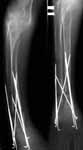

A male 23 y.o. many years sustained severe osteoporosis with multiple fractres of long bones and ribs. Last 4 years was not able to leave chair. Some x-rays attached. What may cause the situation? Juvenile osteoporosis should have been recovered spontaneously to date. What lab research is needed? What is most likely diagnosis? Can such fractures be treated more aggressively? What medications can improve bone quality? Biphosphonates? Somatotropin?